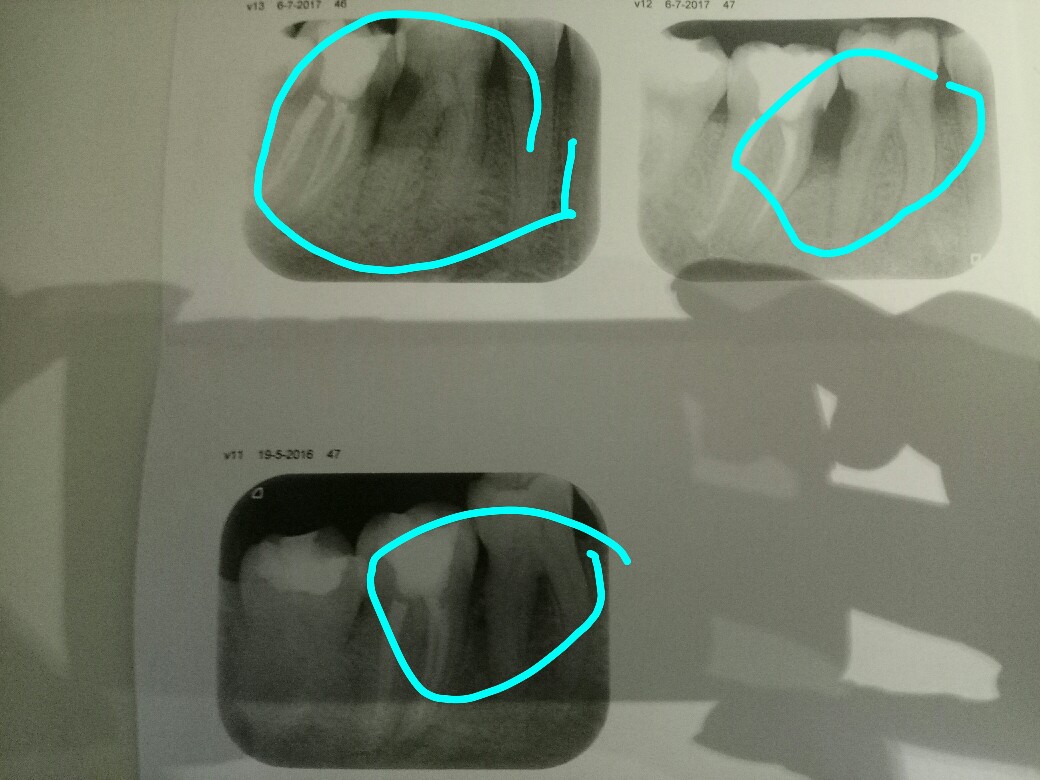

Gisteren na twee weken kiespijn toch maar naar de tandarts gegaan. Nu schijnt er een gaatje te zitten tussen twee kiezen en moet de kies er uit gehaald worden bij de kaakchirurg. Volgens de tandarts is het niet mogelijk om te vullen want ze komen er niet bij. Voordat ik een afspraak ga maken bij de kaakchirurg wil ik toch even hier vragen of er geen andere mogelijkheid is! Ik heb een foto toegevoegd zodat jullie een duidelijk beeld hebben.

"Mijnheer kwam bij mij met pijnklacht 46/47, op de foto bleek een forse caviteit in de 46distaal te zitten. Het element is helaas verloren en graag wil ik jou vragen de extractie uit te voeren ivm grote kans op breuk, en dan vnml van de mesiale wortel."